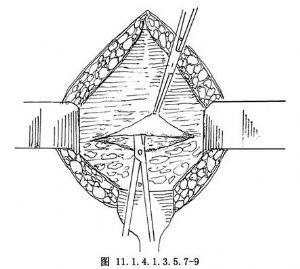

11.2 2.分離腹膜膀胱間隙

同腹膜外剖宮產術,可用側入法或頂入法。於膀胱頂部下1~2cm處橫行切開膀胱筋膜,深達膀胱肌層,切口向兩側延長(圖11.1.4.1.3.5.7-8)。以鉗子提起膀胱筋膜上緣,分離、下推膀胱,先向上分離達膀胱頂部(圖11.1.4.1.3.5.7-9),再向下分離達膀胱腹膜反折(圖11.1.4.1.3.5.7-10)。此處可見臍中韌帶和臍旁韌帶,視其組織厚薄進行切斷縫扎(圖11.1.4.1.3.5.7-11)。